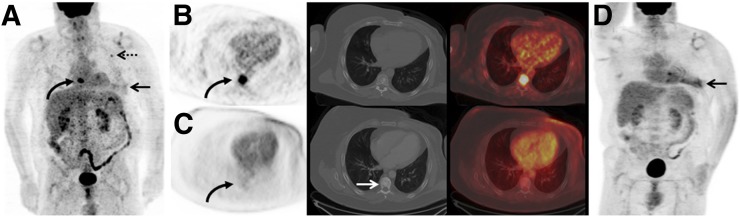

FIGURE 2.

A 53-y-old man with a pre-PET/CT stage IIB breast cancer, which was upstaged to stage IV by 18F-FDG PET/CT. (A) 18F-FDG maximum-intensity-projection image demonstrates 18F-FDG avidity in left breast (arrow), left axilla (dashed arrow), as well as overlying midline chest (curved arrow). (B) Axial 18F-FDG PET, CT on soft-tissue window, and fused 18F-FDG PET/CT demonstrate the 18F-FDG–avid known primary left breast malignancy (arrow). (C) Axial 18F-FDG PET, CT on soft-tissue window, and fused 18F-FDG PET/CT demonstrate 18F-FDG–avid known left axillary nodal metastases (dashed arrow). (D) Axial 18F-FDG PET, CT on bone window, and fused 18F-FDG PET/CT demonstrate 18F-FDG avidity in midline chest on the maximum-intensity-projection image corresponding to a thoracic vertebra without CT correlate. This lesion was biopsied and proven to be a previously unsuspected osseous metastasis, increasing patient’s stage to IV. This altered patient’s management from surgical management to systemic therapy without surgical management.

FIGURE 3.

A 58-y-old man with a pre-PET/CT stage IIB breast cancer, which was upstaged to stage IV on 18F-FDG PET/CT. (A) 18F-FDG maximum-intensity-projection image demonstrates mild 18F-FDG avidity in left mastectomy bed (arrow) and left axillary node (dashed arrow), as well as overlying midline chest (curved arrow). (B) Axial 18F-FDG PET, CT on bone window, and fused 18F-FDG PET/CT demonstrate an 18F-FDG–avid thoracic vertebra (curved arrow) corresponding only with small, benign-appearing sclerotic focus on CT. This patient was subsequently treated with systemic therapy. (C) Axial 18F-FDG PET, CT on bone tissue window, and fused 18F-FDG PET/CT after systemic therapy demonstrate resolution of 18F-FDG avidity (curved arrow) and increased sclerosis of the vertebra (white arrow), consistent with therapy response in an osseous metastasis and osseous healing. (D) 18F-FDG maximum-intensity-projection image after systemic therapy demonstrates persistence of 18F-FDG–avid postmastectomy inflammation (arrow) but resolution of avidity in the node and osseous metastasis.

The probable impact of systemic staging with 18F-FDG PET/CT can be seen in Figures 2 and 3. The patient in Figure 1 was initially stage IIB and underwent 18F-FDG PET/CT at initial staging, before any therapy. 18F-FDG PET/CT revealed unsuspected distant metastases, and thus stage IV disease. The treatment plan for this patient was changed from surgical management to systemic therapy without surgical management. The patient in Figure 2 was also initially stage IIB and underwent 18F-FDG PET/CT after mastectomy but before further systemic or radiation therapy. 18F-FDG PET/CT reveled unsuspected distant metastases, and thus stage IV disease. If the 18F-FDG PET/CT had been performed before mastectomy, surgical management may have been foregone in lieu of systemic therapy.